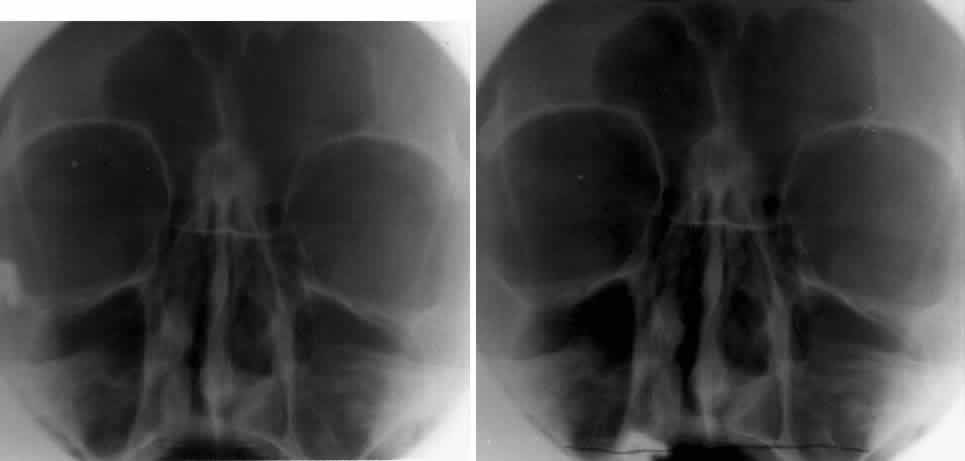

The optic foramen should measure 6 mm vertically and 5 mm horizontally. Asymmetry greater than 1 mm or a vertical dimension greater than 6.5 mm is considered abnormal.15,27 Ninety-eight percent of patients have optic canals that vary by less than 1 mm.27 Concentric enlargement of the foramen and optic canal can be seen with optic nerve gliomas, meningiomas, neurofibromatosis, and less commonly an aneurysm of the ophthalmic artery (Fig. 16). A decrease in the optic foramen and canal dimension can be seen in fibrous dysplasia, Paget's disease, hyperostosis secondary to a meningioma, or microphthalmos (Fig. 17, Table 1).

Fig. 16. Oblique apical projections showing the optic foramen. The left optic foramen has concentric enlargement from an optic nerve glioma. The foramen should not have greater than 1 mm of asymmetry.

Fig. 17. Bilateral optic canal compression from fibrous dysplasia. There is diffuse bone thickening in each orbit. Note small size of optic foramen (arrow).